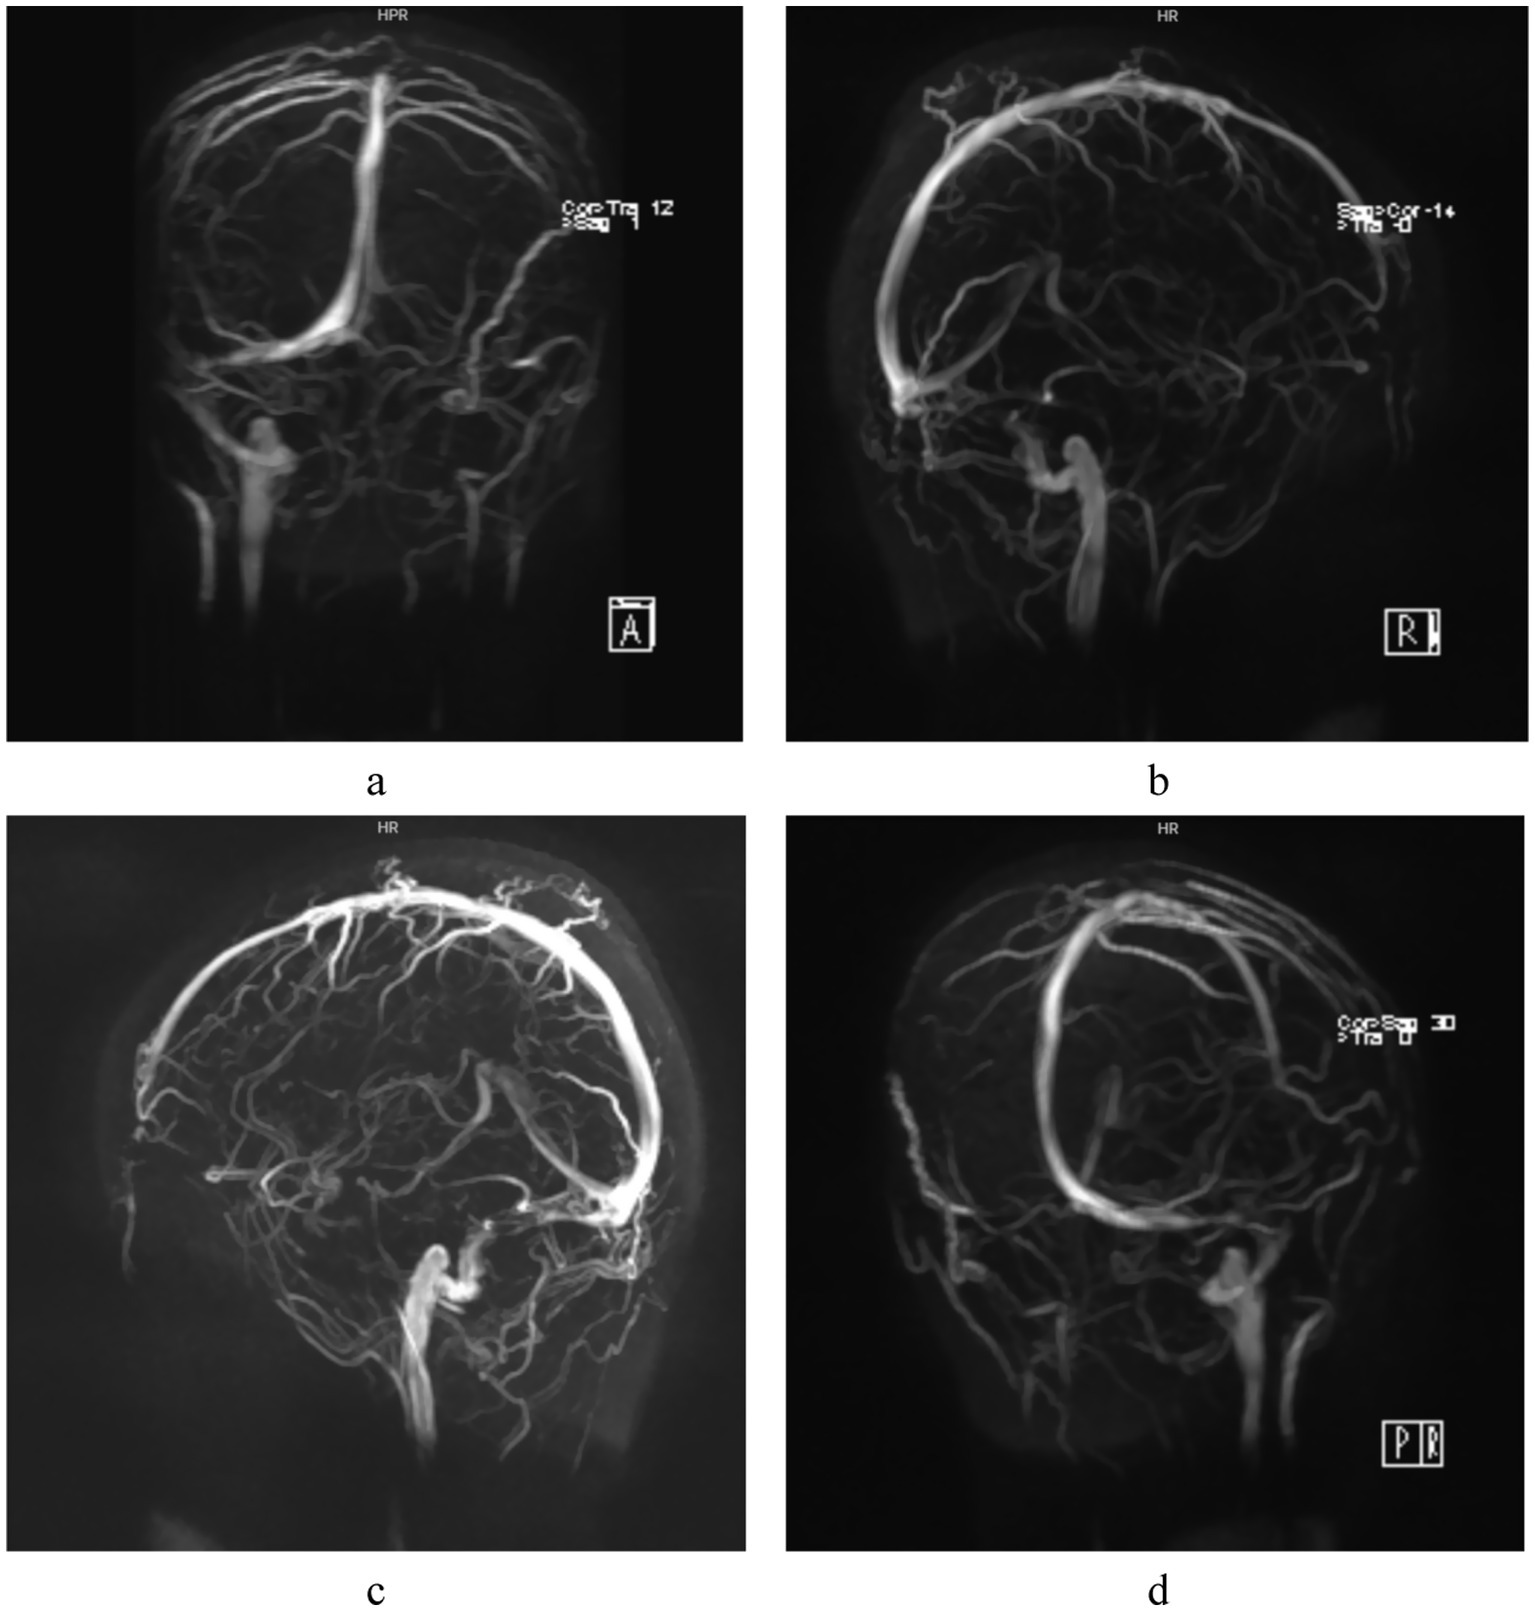

Figure 4

MRV examination: Focal narrowing of the right distal sigmoid sinus and proximal transverse sinus is demonstrated in different angles (a-d), no imaging of the left sigmoid sinus and transverse sinus is visualized.

The patient was a 28-year-old female who presented with decreased vision in the right eye postpartum. Fundus examination revealed bilateral papilledema. She reported no redness or eye pain, no dizziness, headache, nausea, vomiting, or pulsatile tinnitus. Due to elevated immune indicators during pregnancy, she had been taking hydroxychloroquine orally for over 5 months, which was discontinued a week prior. One month ago, the patient was diagnosed with lower extremity venous thrombosis accompanied by elevated D-dimer levels. She received systemic anticoagulation therapy with subcutaneous injection of low molecular weight heparin at a dose of 200 IU/kg administered once daily. This therapy was continued until the day prior to delivery. Post-delivery, the patient’s anticoagulant regimen was switched to oral rivaroxaban tablets at a dosage of 10 mg daily. A cesarean section was performed 3 days prior. Her pre-pregnancy weight was 45 kg (BMI 16.5), and postpartum weight was 60 kg (BMI 22). Her blood pressure remained normal, with no history of gestational hypertension or diabetes. One year ago, she was diagnosed with intracranial hypotension syndrome due to “headache” and underwent cerebrospinal fluid leakage repair. There was no significant family or other medical history. Physical examination showed normal muscle tone and strength in the extremities, and normal deep and superficial sensation. Uncorrected visual acuity was 0.6 in the right eye and 1.0 in the left. Slit-lamp examination of the anterior eye segments revealed no abnormalities but showed vitreous opacity and posterior detachment. The physiological blind spots in both eyes’ visual fields were enlarged. Fundus photography (Figure 1) showed prominent papilledema with blurred edges, tortuous and dilated peripheral veins, and patchy bleeding in both eyes. OCT (Figure 2) revealed partial edema from the macular to the optic-disk area in the right eye, with minor exudation and retinal thickening. The left eye’s macular area showed no significant abnormalities. Blood tests indicated D-dimer >20 mg/L, erythrocyte sedimentation rate 78 mm/h, antinuclear antibody 333.10 AU/mL, weakly positive anti-SSA/Ro52 and anti-SSA/Ro60 antibodies, complement C3 1.81 g/L, and C4 0.83 g/L, anti-double-stranded DNA antibodies were negative, the lupus screening ratio was normal, anticardiolipin antibodies were normal, and no other blood tests were significantly abnormal. To rule out other secondary causes of increased intracranial pressure, an MRI was performed, but it revealed no significant abnormalities. We advised the patient to undergo lumbar puncture to measure intracranial pressure. However, due to her puerperal status and previous history of low intracranial pressure, she was concerned about the risk of lumbar puncture-induced cerebrospinal fluid leakage and disagreed with the high intracranial pressure diagnosis. Ophthalmic color Doppler ultrasound demonstrated bilateral optic nerve sheath widening, with measurements of 0.625 cm on the right and 0.590 cm on the left (Figure 3), suggesting potential elevated intracranial pressure. Lower extremity venous color Doppler ultrasound revealed thrombosis in one of the left posterior tibial veins. MRV examination (Figure 4) showed focal thinning of the right distal sigmoid sinus and proximal transverse sinus, non-visualization of the left sigmoid sinus and transverse sinus, and thinning of the left distal internal jugular vein. We concluded that the patient’s increased intracranial pressure, leading to bilateral papilledema, was caused by a combination of pregnancy-related physiological changes, blood hypercoagulability, immune abnormalities, and intracranial venous sinus structural anomalies. Treatment with mannitol to reduce intracranial pressure, along with microcirculation improvement, neurotrophic therapy, and systemic anticoagulation, was administered. After 1 week, visual acuity improved, with uncorrected visual acuity reaching 1.0 in both eyes. Fundus reexamination showed alleviated tortuous dilation of the bilateral peripapillary veins, reduced and absorbed bleeding, gradually decreased exudation, and slowly improving papilledema (Figures 1, 2). In the right eye, macular edema resolved, exudation gradually decreased, retinal thickness returned to normal, and the ellipsoid zone was partially absent and broken (Figure 2). The left eye’s macular area showed no apparent abnormalities (Figure 2), and the patient continues to receive further treatment.

Autoimmune diseases are important risk factors for CVST (16, 17). Autoimmune inflammatory activation may contribute to intracranial venous sinus inflammation via vascular endothelial injury. Thrombotic events occur in 10–20% of SLE patients (18), resulting from lupus anticoagulant deposition combined with immune-mediated vasculitis (19). Elevated antinuclear antibodies, weakly positive anti-SSA antibodies, and increased C3 and C4 levels may play roles in pregnancy-related cerebral venous sinus thrombosis. Pregnancy and puerperium are the most common risk factors for CVST (20, 21). The hypercoagulable state of blood and venous stasis, along with a significant increase in fibrinogen and coagulation factors, and a significant decrease in antithrombin III and plasminogen, increase the risk of CVST (22). Based on the patient’s comprehensive clinical data, including postpartum hypercoagulable state, venous stasis, D-dimer level >20 mg/L, previous history of lower extremity venous thrombosis, abnormal immune biomarkers, and MRV revealing focal stenosis of the distal right sigmoid sinus and proximal transverse sinus, agenesis of the left sigmoid sinus and transverse sinus, and stenosis of the distal internal jugular vein, collectively these findings suggest the presence of occult microembolic obstruction and mild venous luminal narrowing. These may reduce blood flow in the right transverse and sigmoid sinuses. The underdevelopment of the left venous sinus could be due to complete thrombotic occlusion or congenital factors, as the left lateral sinus is typically hypoplastic. Jianu et al. (23) observed that IIH often occurs following thrombosis of the right lateral sinus. Arias-Moeller et al. (24) demonstrated that patients with CVST complicated by contralateral dysplastic venous sinuses have a significantly higher risk of developing intracranial hypertension. The pathogenesis of intracranial hypertension in this patient is further complicated by a prior history of intracranial hypotension repair surgery, which inherently adds diagnostic complexity and clinical challenges. CVST frequently occurs as a secondary consequence of intracranial venous sinus stenosis (25), with the latter serving as a key predisposing factor for the former. Both intracranial venous sinus thrombosis and stenosis can impair venous return, thereby increasing venous sinus pressure (26). This pressure elevation disrupts CSF resorption mechanisms, leading to CSF accumulation and a subsequent gradual increase in intracranial pressure (27). The resulting pressure imbalance within the optic nerve sheath promotes papilledema formation, ultimately establishing a vicious cycle of “stenosis-pressure-sinus wall collapse-stenosis exacerbation.” The causal relationship between venous sinus stenosis and increased intracranial pressure remains unclear (28). Rohr et al. (29) suggested that venous sinus stenosis impedes CSF reflux, affecting CSF absorption by arachnoid granulations and elevating intracranial pressure. Conversely, Puffer et al. (30, 31) posited that increased intracranial pressure compresses the venous sinuses, reducing their compliance and causing sinus wall collapse. Regardless of whether venous sinus stenosis is the cause or consequence of IIH, venous sinus hypertension is a key factor in exacerbating cerebral circulatory disorders (32). Although lumbar puncture was not performed herein, ophthalmic color Doppler ultrasound showed bilateral optic nerve sheath widening, about 0.625 cm on the right and 0.590 cm on the left, which supported the diagnosis of intracranial hypertension. Multiple studies (33–36) have established ocular ultrasound as a reliable non-invasive diagnostic tool for assessing intracranial pressure changes. It can effectively evaluate intracranial pressure via the optic nerve sheath diameter with good sensitivity, offering a safer and more effective alternative to invasive lumbar puncture. The limitation is that ophthalmic color Doppler ultrasound is strongly operator-dependent. Cimilli Ozturk et al. (37) showed that there were differences in measurements between operators, which means that examination results may vary depending on the experience and skill of the operator.